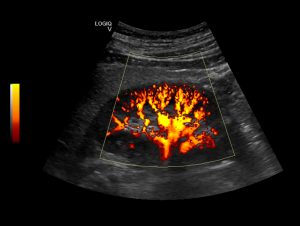

Kidney

3. Kidney (Urinary Tract) Scans

4. Kidney